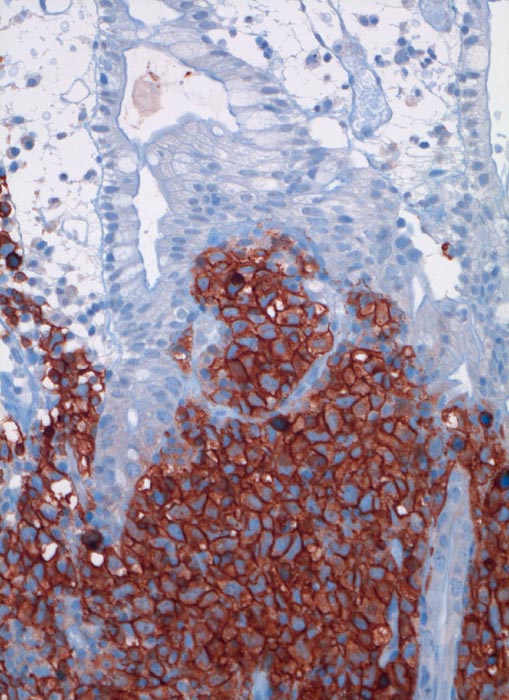

extranodales diffuses grosszelliges B-Zell Lymphom (WHO)

Ileum

Die CD20 positiven Lymphomzellen infiltrieren die Mukosa.

Immunhistochemie: CD20 positiv, CD3 und CD30 negativ, CD117 negativ

Akute Peritonitis bei Darmperforation

Immunhistochemie

CD20 (L26)

200